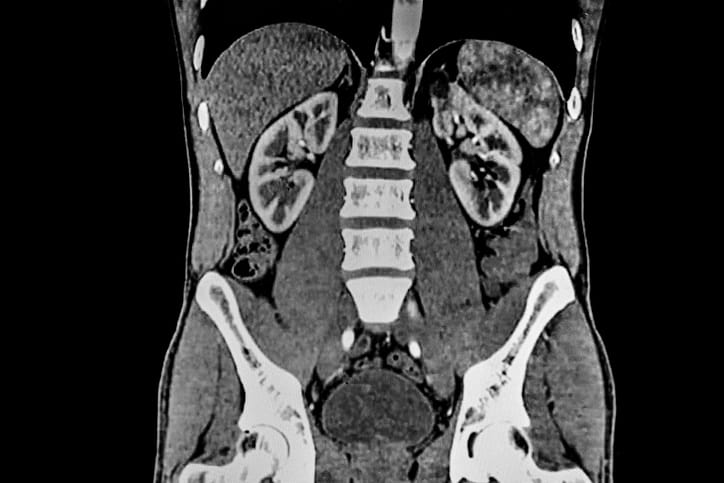

A computed tomography (CT) scan is a diagnostic tool that allows medical professionals to gain a clear view of what’s happening inside your body. CT scans are similar to X-rays; however, CT scans capture images from all angles, and sophisticated software compiles those images to generate three-dimensional images of parts of your body. The detailed images produced by abdominal CT scans provide practical diagnostic information that can be used to identify health issues such as hernias, kidney stones, and several types of cancer.

Once the table moves you into position, the scanner moves around you, capturing images of the body from all angles. These images are transferred to a computer that combines them, providing three-dimensional images of what’s happening inside your body.

A CT technologist oversees the CT scan, providing guidance throughout to ensure that all necessary images are captured, generating comprehensive images of your organs (including your intestines, kidneys, liver, and pancreas), bones, and blood vessels.